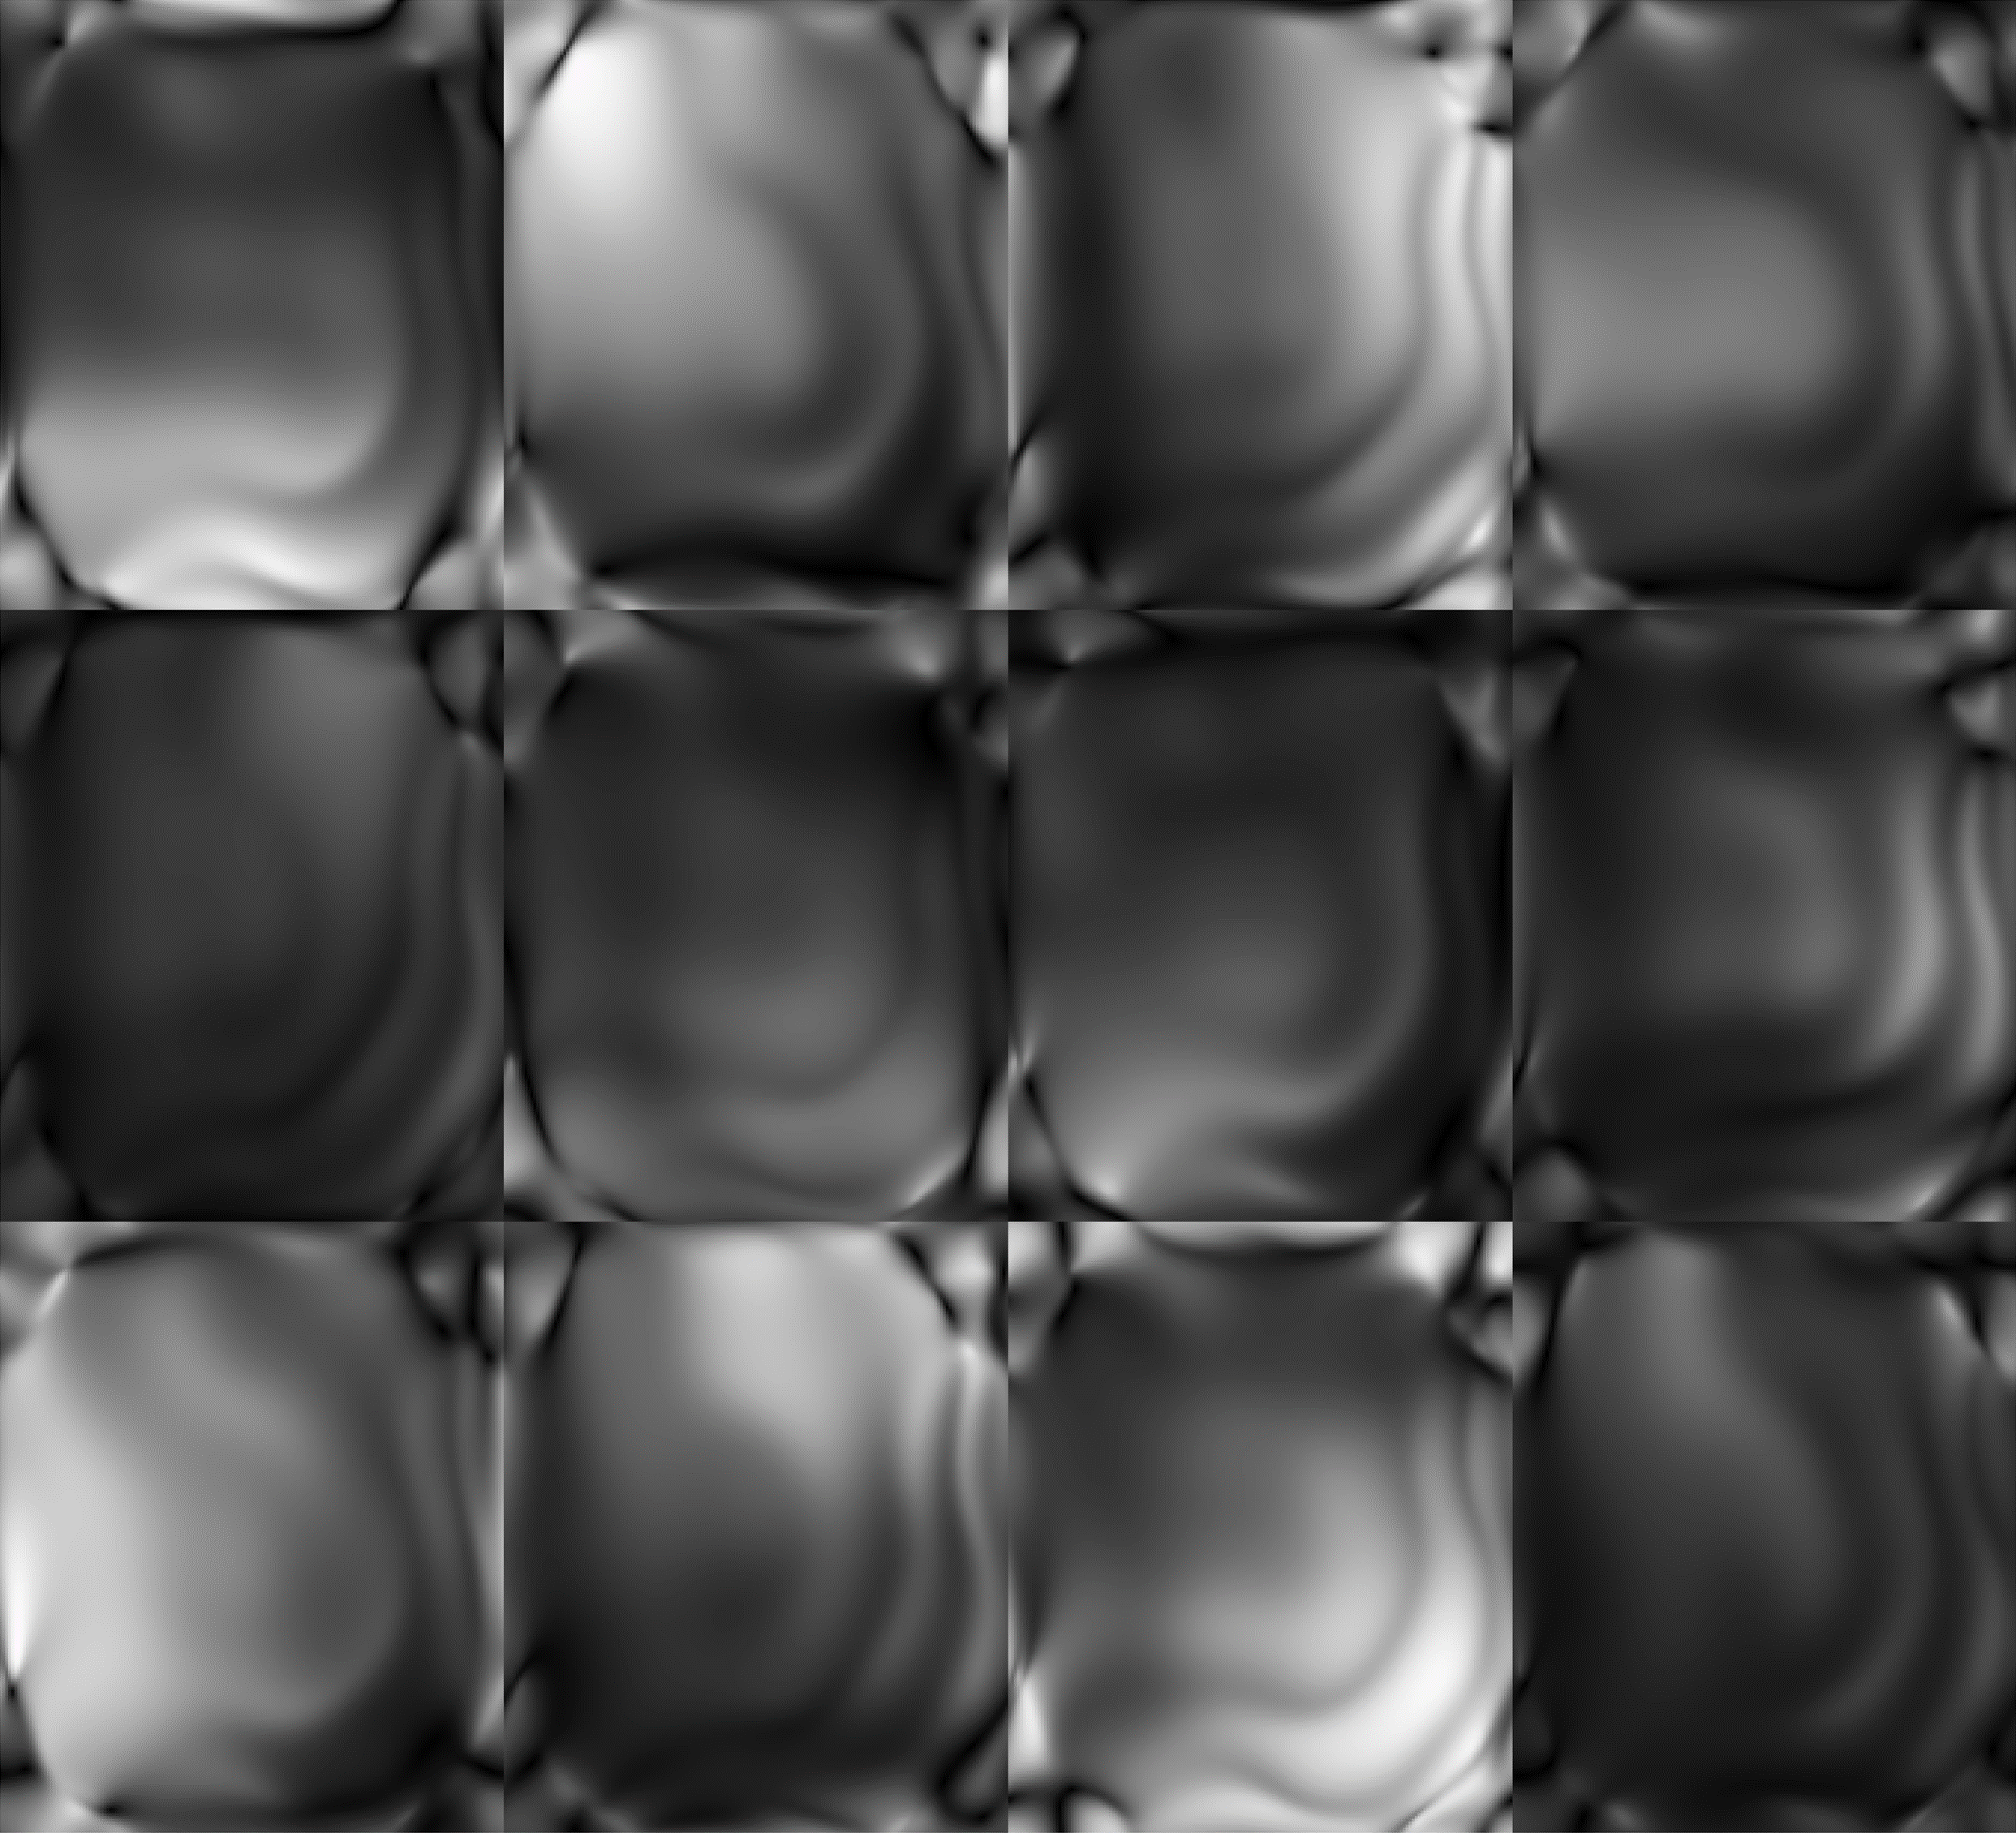

Example reconstructions of brain data are shown in Fig. 5(a) and Fig. 5(b), from the CC359 dataset, and Fig. 6(a) and Fig. 6(b), from the fastMRIBrain dataset. Figure 7 shows example reconstructions of knee data from the StanfordKnee dataset.

Refer to caption

Figure 7: Reconstructions of 8-coil T2-weighted Fast-Spin Echo data from the Stanford Knee dataset undersampled with a Gaussian 2D sampling pattern for 12x acceleration. The top row-first column shows the ground truth (Target) image. SSIM and PSNR scores are reported for each method and computed against the Target image. Methods are sorted alphabetically.